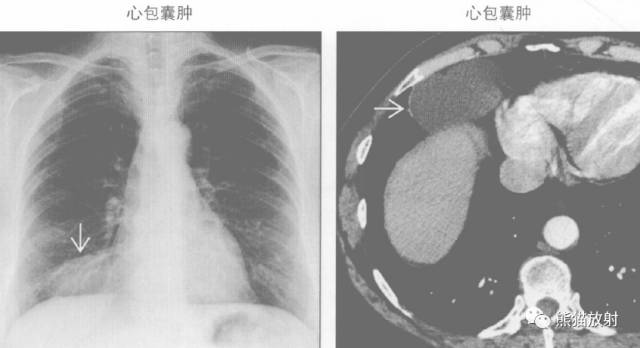

“纵隔囊性肿块”的鉴别诊断

纵隔囊性肿块